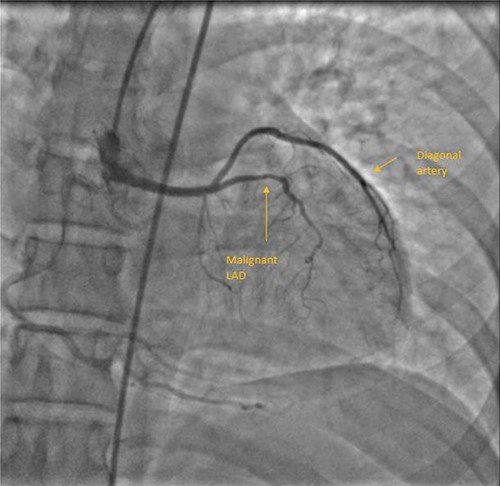

A 55-year-female diagnosed of having malignant LAD course 10 years back. She was fairly asymptomatic at that time and chose not to be operated. Two things changed over the next few years. She developed chest discomfort at physical activity lower than what she could previously tolerate, also developing calculous cholecystitis for which she needed to be operated. Although the motive for her to be able to undergo cholecystectomy was stronger than her exertional chest discomfort, she was well counselled and scheduled for surgery. Through median sternotomy, LIMA harvested and after cardioplegic cardiac arrest initially aortotomy done to confirm coronary origins. LAD and LCx had origination from RSOV. LAD from separate ostium, common LCx and RCA origin. Mid LAD segment was intramyocardial and bridging was released following LIMA-LAD anastomosis. Proximal LAD ligated after initial test ligation. She had an uneventful postoperative period and discharged on seventh postoperative day (POD). Figure 1 shows her CAG.